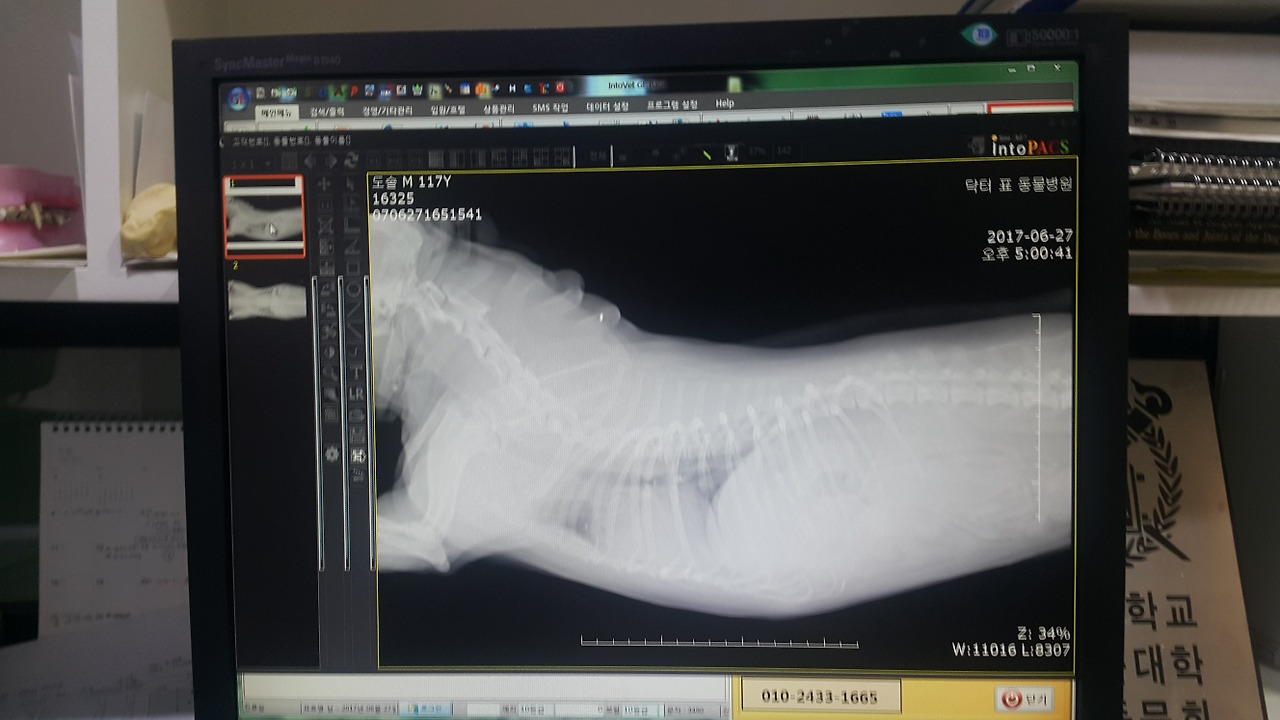

도솔이의 병명은 <심장 이첨판 폐쇄 부전증>이고, 3기에 해당한다고 했다.

심장판막에 문제가 생겨 울혈성 심부전이 발생하는 질환으로 폐에 물이 차게 되는 합병증을 동반하는 질환이라는 것이다.

한마디로 고칠 수 없는 심장병이란 말이었다.

도솔이 동물병원 엑스레이 검진.

심장의 울혈 증상을 완화시키는 약과 폐에 찬 물을 배출시키는 이뇨제를 도솔이에게 하루 3번 정해진 시간마다 먹여야 했다.

그리고 도솔이의 호흡이 가빠졌을 땐 응급 상태의 경중을 파악하여 이뇨제 약을 추가로 투약하는 것이 바람직하다고 주치의 선생님으로부터 권고받았다.